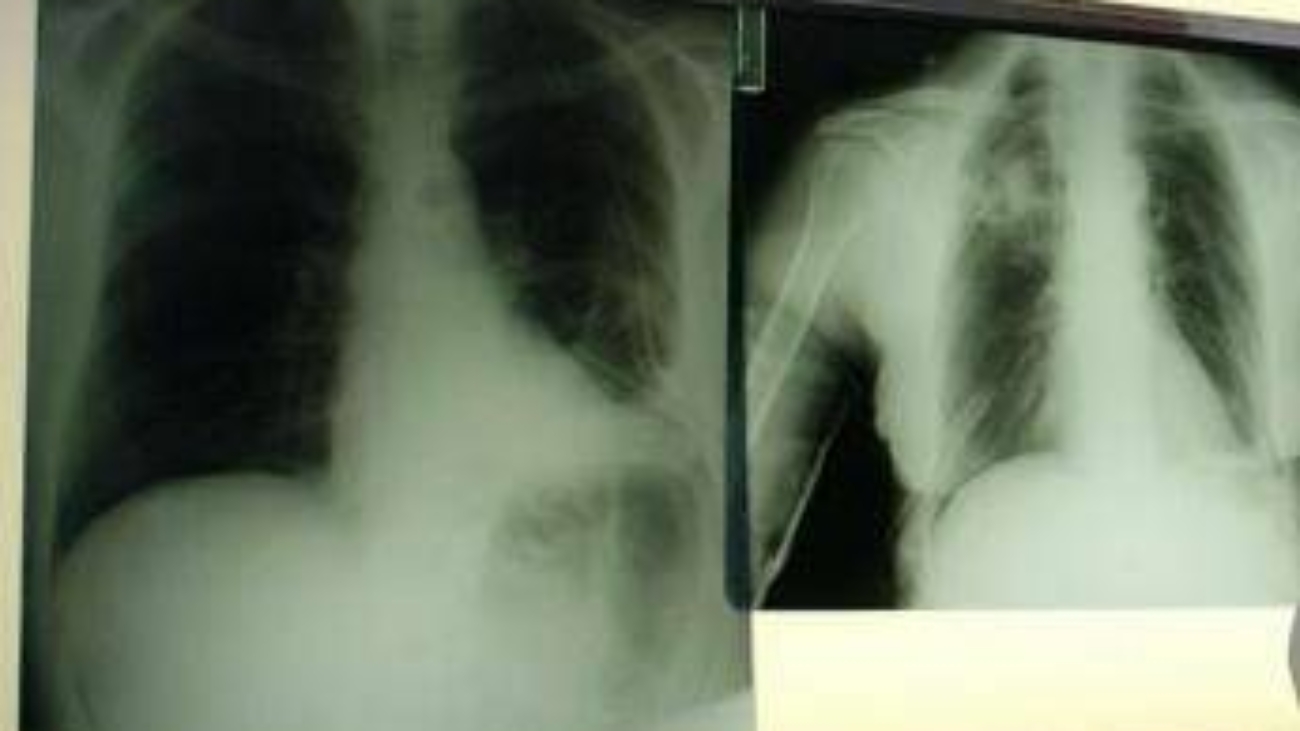

Apnea ostruttiva del sonno, rischi per il cuore si moltiplicano: sintomi

(Adnkronos) – La prevalenza di obesità e sovrappeso tra le persone che convivono con il disturbo è compresa tra il 40% e il 70%, e chi è obeso ha maggiori probabilità di soffrirne in forma più grave rispetto a chi non lo è